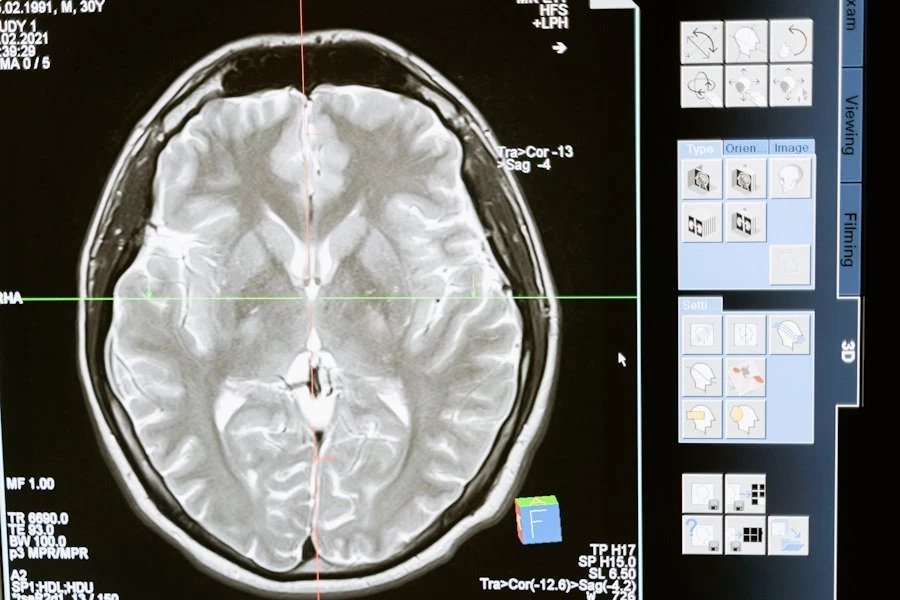

Neuralink, разработчик мозговых чипов-имплантатов, уже в текущем году проведёт первые испытания на человеке. Информацией, на форуме VivaTech, проходящем в Париже, поделился глава компании Илон Маск. Он добавил, что пациентом для имплантации чипа станет человек с параличом ног. Он сказал, что первый случай возможен в этом году.

Neuralink лишь недавно получил «добро» от регулирующих органов США на проведение клинических испытаний на человеке. Учитывая расследования, с которыми компания столкнулась в стране из-за проведения опытов на животных — это огромное достижение для неё. FDA дало разрешение Neuralink на использование их мозгового имплантата и робота-хирурга для испытаний, но детали разглашать отказалась.